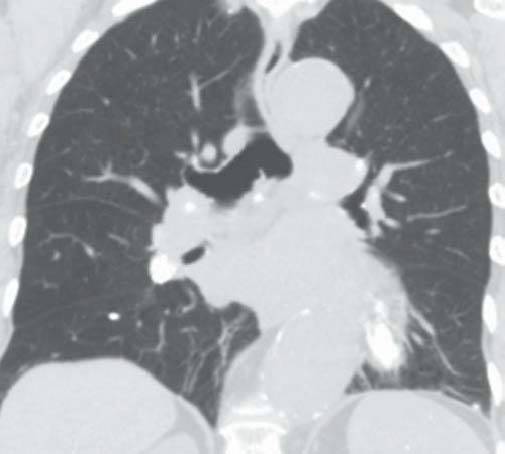

男性,48岁,以肺结节就诊。

D

图A和B为轴位CT平扫,示肝、脾内多发大小不一的钙化,肝、脾大小形态正常,图C和D为冠位重组纵隔窗及肺窗,示纵隔、肺门淋巴结钙化及肺的钙化结节,同时发现主动脉瘤。

组织胞楽菌病是美国中部的一种地方病,自艾滋病流行以来,本病发病率明显上升,在非流行地区也有报道。大多数组织胞浆菌病患者伴有纵隔淋巴结肿大、钙化(如本例所示),可引起纵隔压迫症状。患者腹部CT扫描可见散布的组织胞浆菌病,肝大(63%)、脾大(38%)、弥漫性脾密度减低(19%)、双侧肾上腺肿大、淋巴结肿大(44%)。在美国,治愈的组织胞浆菌荚膜感染是引起弥漫性脾钙化的最常见原因,引起多发脾钙化的其他原因有治愈的结核、布鲁杆菌病及肺囊虫感染、血管瘤、静脉石、含铁血黄素沉着症、镰状红细胞贫血和含铁结节(G-G小体)。